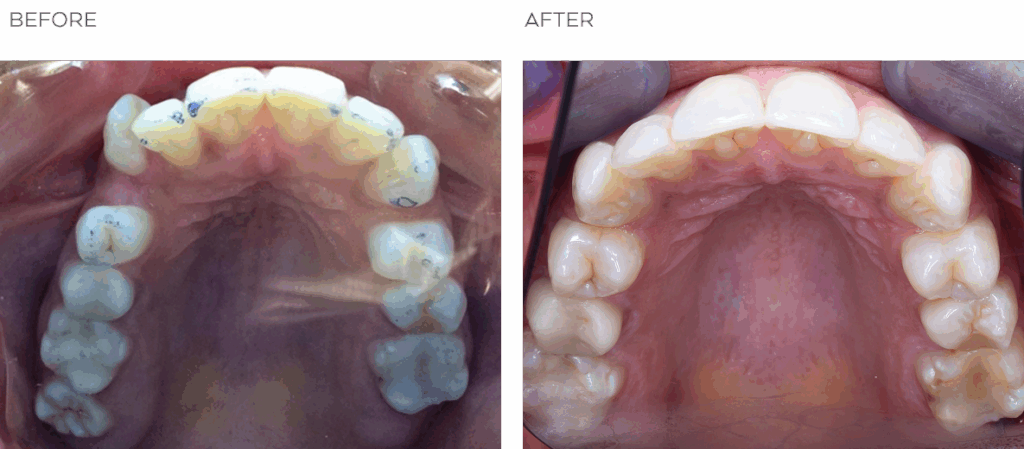

Nathalie came to see NYC dentist and Invisalign specialist Dr. Lena Sapozhnikoff because she had a severely misaligned canine that she wanted to fix. She also had never lost her baby canine on that side—it was impacted and hanging in there behind her permanent canine, way beyond its welcome! Dr. Lena extracted the baby tooth and was able to give Nathalie a stable bite and a strikingly beautiful smile using Invisalign along with a very cool technology called Propel Accelerated Orthodontics. Dr. Lena takes a different approach to orthodontics, which you’ll see makes her the best choice for Invisalign in NYC.

The first order of business, of course, was to extract Nathalie’s baby tooth that never fell out so that she would have the same number of teeth on both sides. Next, Dr. Lena got her started on Invisalign treatment to bring the teeth into alignment, along with elastics to help move things along. Nathalie was a model patient, wearing the elastics exactly as instructed and being present and punctual for all her appointments. This type of compliance really helps patients get better results faster with Invisalign.